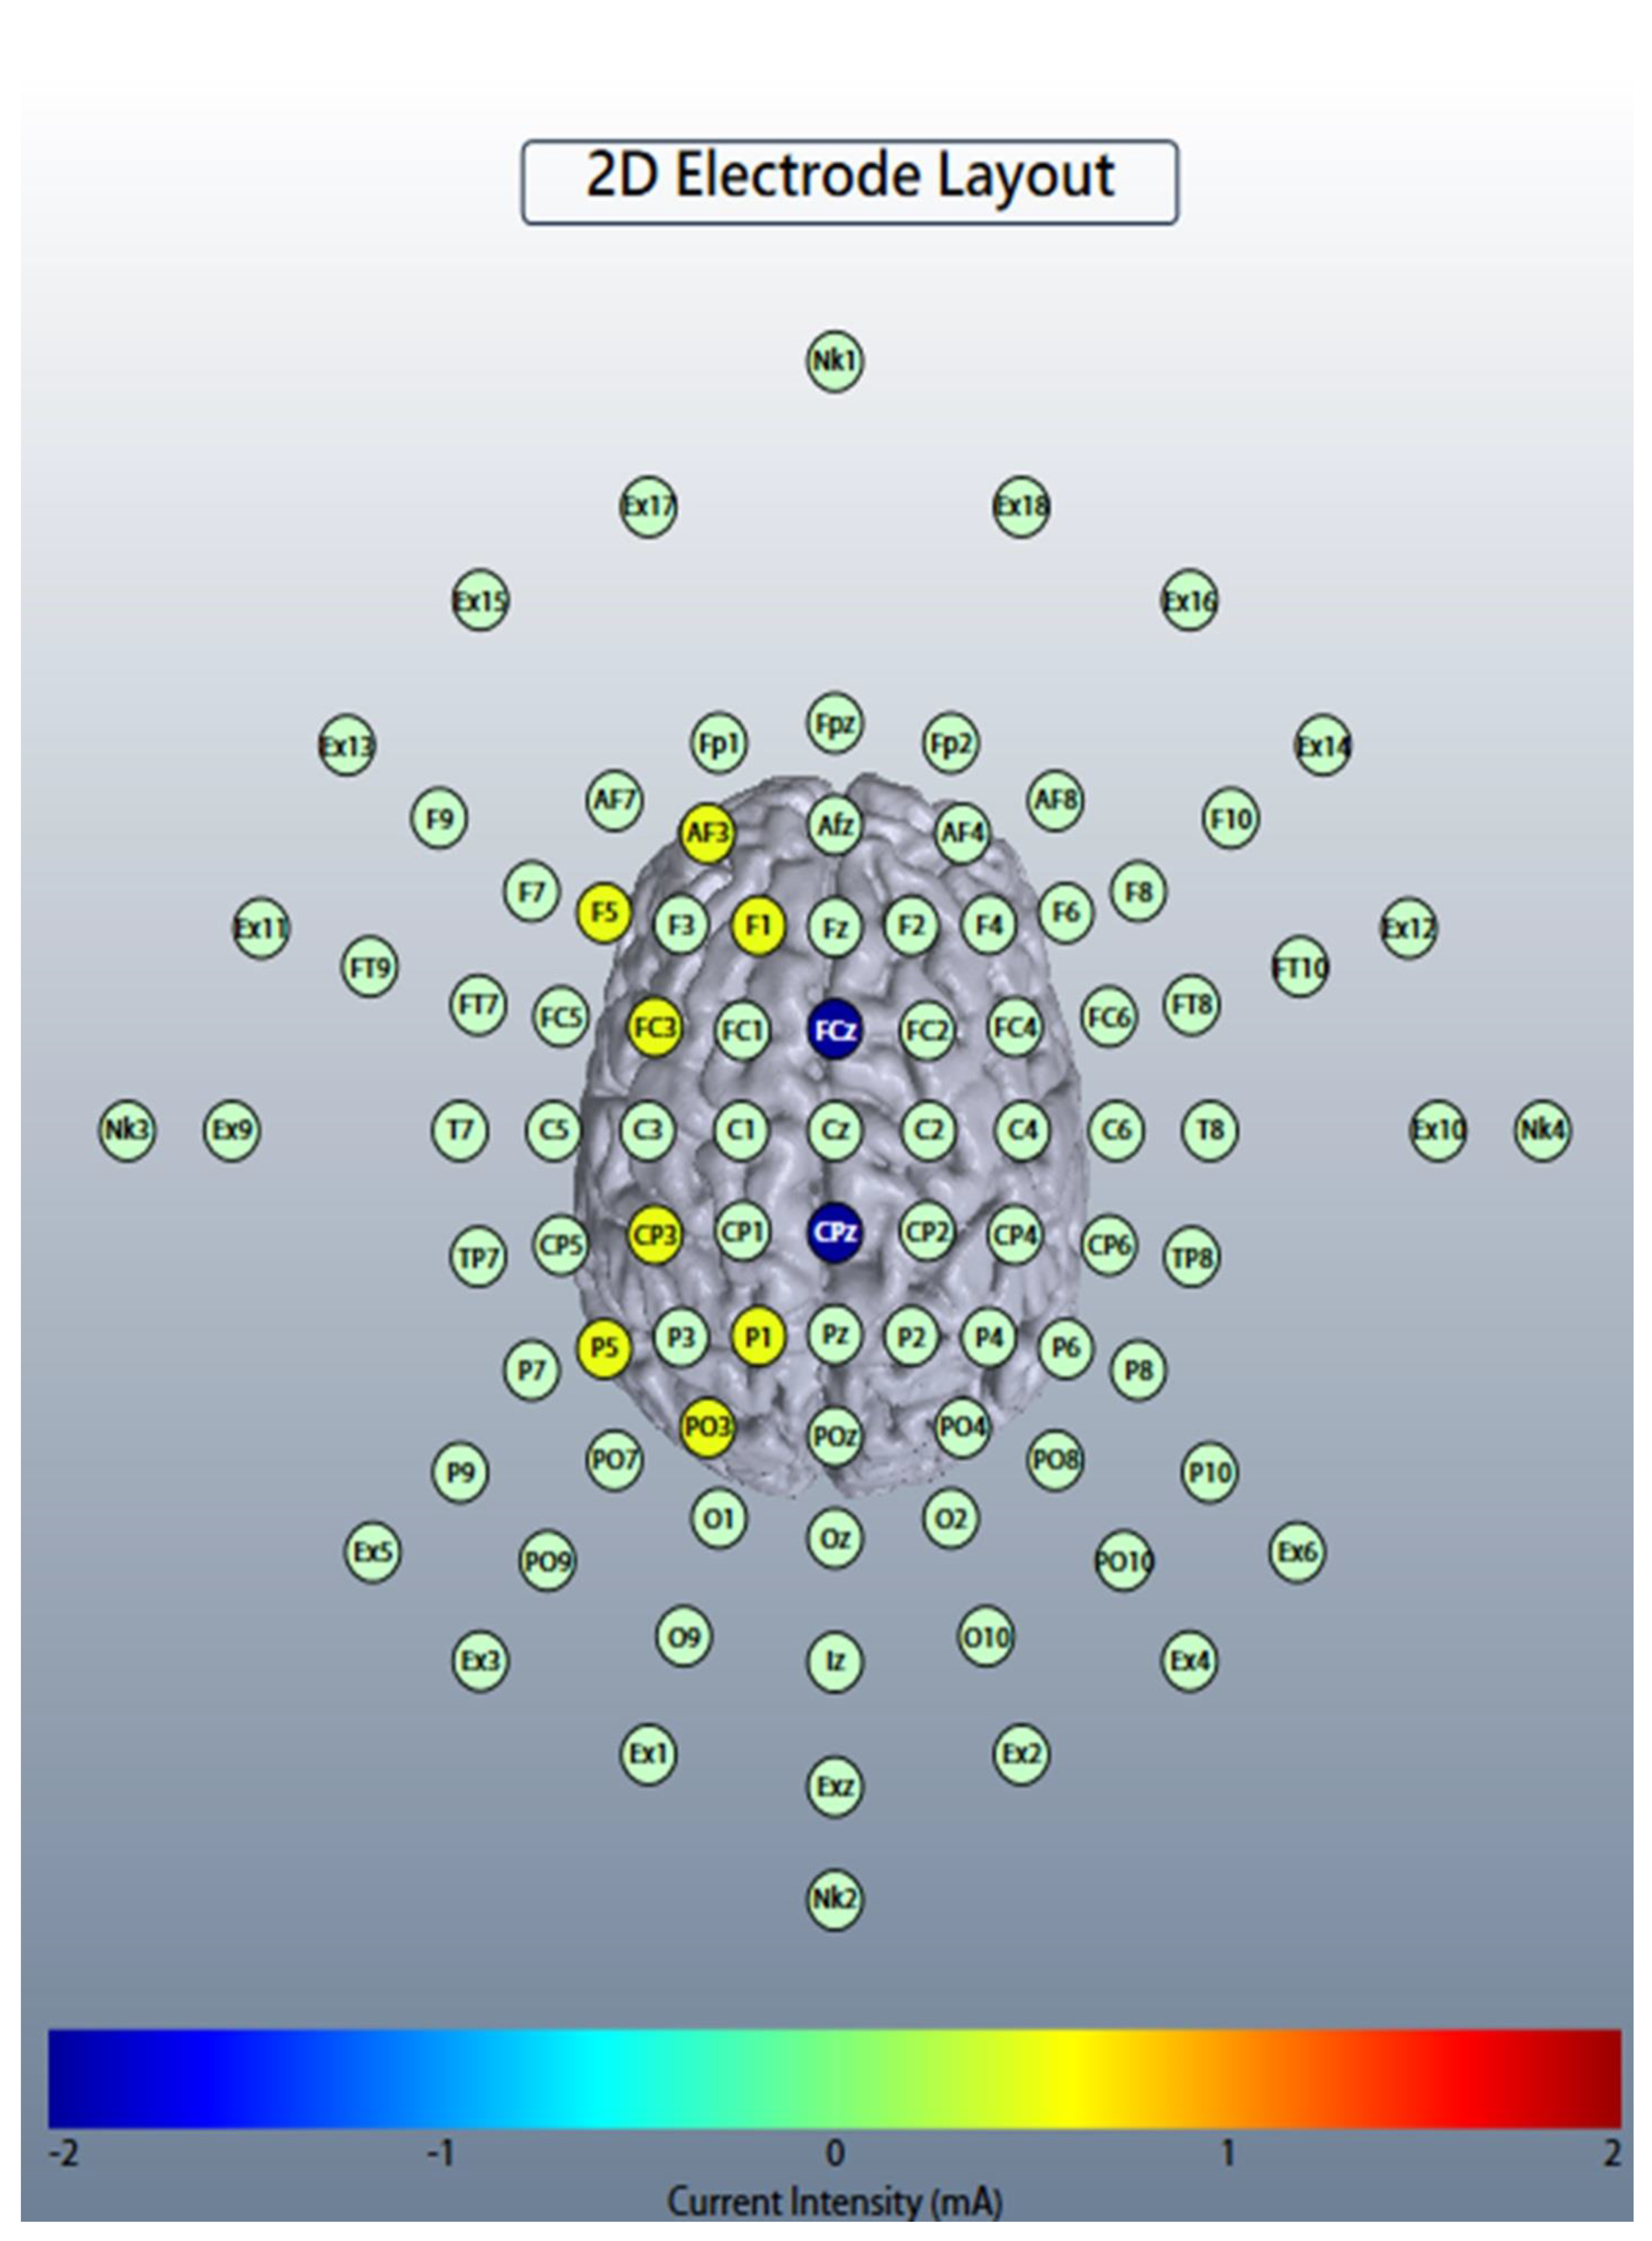

2.2. Online Left-Hemispheric In-Phase Frontoparietal Theta (6 Hz) tACS